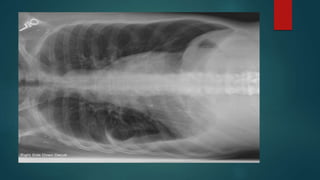

CXR  Lateral decubitus*CXR requires at least 75 ml of fluid  CXR PAV requires at least 150 ml of fluid to be detected  Supine CXR are fallacious to detect pleural effusion  CXR PA view d/ds Subpulmonic effusion Costophrenic and cardiophrenic recesses Blunting of hemidiaphragm Homogenous fluid dense radio-opacity in the lung field and making meniscsus without any bronchovascular markings within Large effusions causes underlying lung collapse and mediastenal shift to opposite side

Exceptionally on CXR Loculated pelural effusion and effsuions in fissures are non dependent  Parapneumonic effusions are difficult to be detected on CXR Grading of effusion on CXR  Mild - Up to causing CoP angle blunting  Moderate - In between  Massive - almost entire hemithorax opaque with collapsed lung